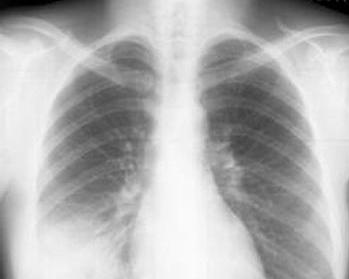

多重肺部感染(multiple microbial pulmonary infections)又称为混合性感染,指两种以上(含两种)病原微生物的肺部感染。多重感染严格意义上指多种病原体均是作为原发性,且是同时发生的感染,不包括一种病原体原发感染和继发另一种病原体感染。多重肺部感染无传染性、无特定感染人群,易引发间质性肺炎、视网膜炎等并发症。[1]